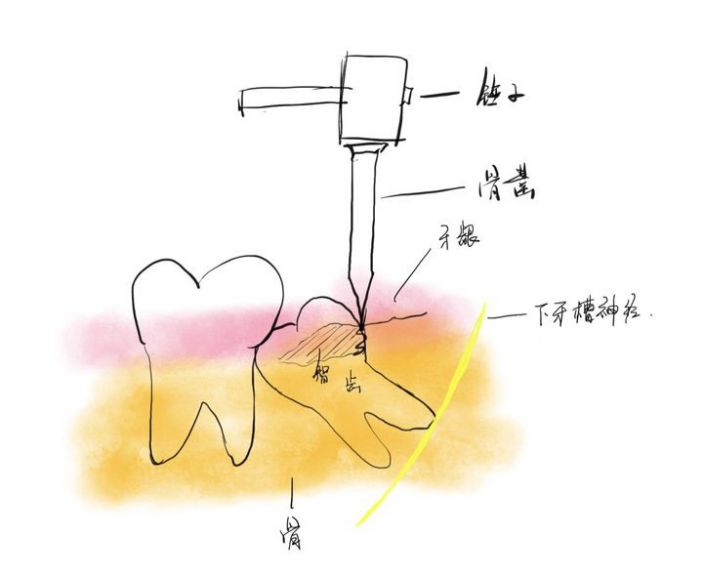

△微創拔牙——準确分割牙體并取出,告别傳統暴力拔牙方式。

張主任講,微創拔智牙融合了多種先進的技術和理念,讓拔牙方式徹底告别盲目、暴力時代,具有這些優勢:1、個性化。術前通過CBCT明确患牙形态、埋伏深度及與下槽骨神經管、鄰牙的關系,分析骨阻力,設計、制定個性化的方案。2、創傷小。根據患牙特征,以減小創傷爲目的設計切口,采用超聲刀、切牙機等先進儀器設備,以小切口暴露牙冠,對患牙進行準确分割後經小切口逐一取出,告别傳統敲、鑿、劈、撬等一系列機械性操作,大幅度減少對正常組織的損傷。3、疼痛小、并發症少、恢複快。微創技術的應用,大幅減少智牙拔除的疼痛以及并發症,加快了術後的恢複。